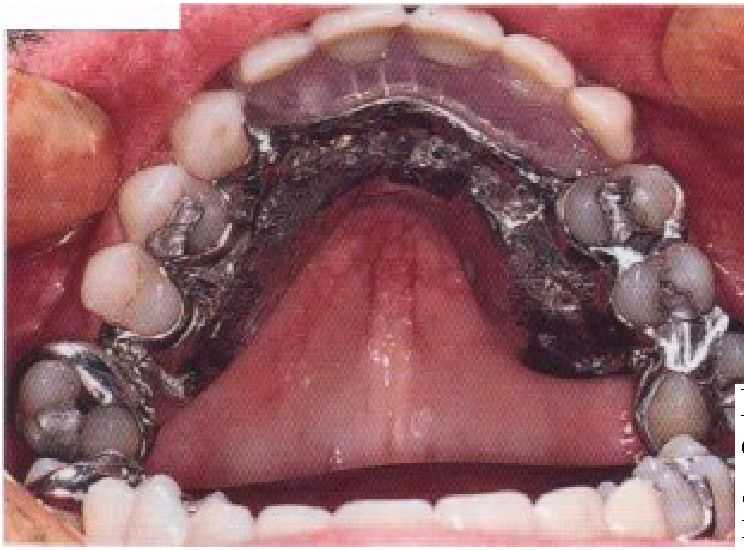

Рис. 5-3. Подковообразная дуга. К сожалению, использование этой дуги часто связано с `

Л

перекрытием десневого края.